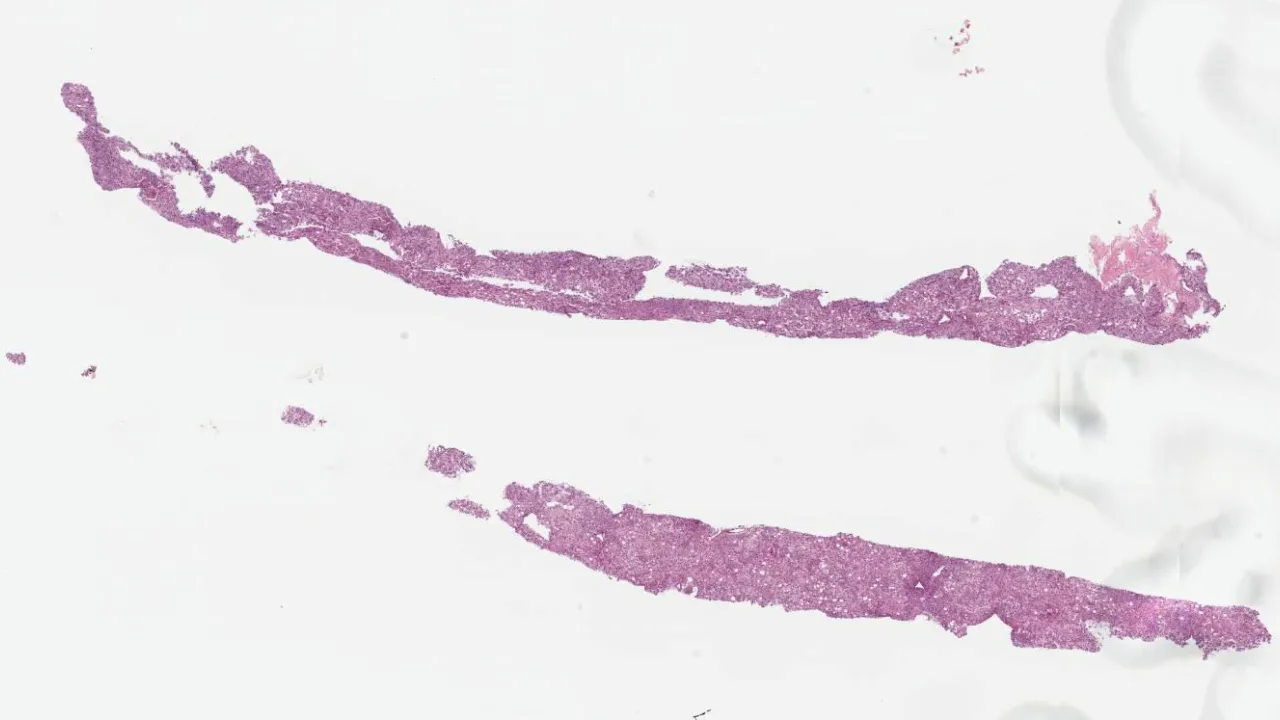

Sural nerve, Necrotizing vasculitis